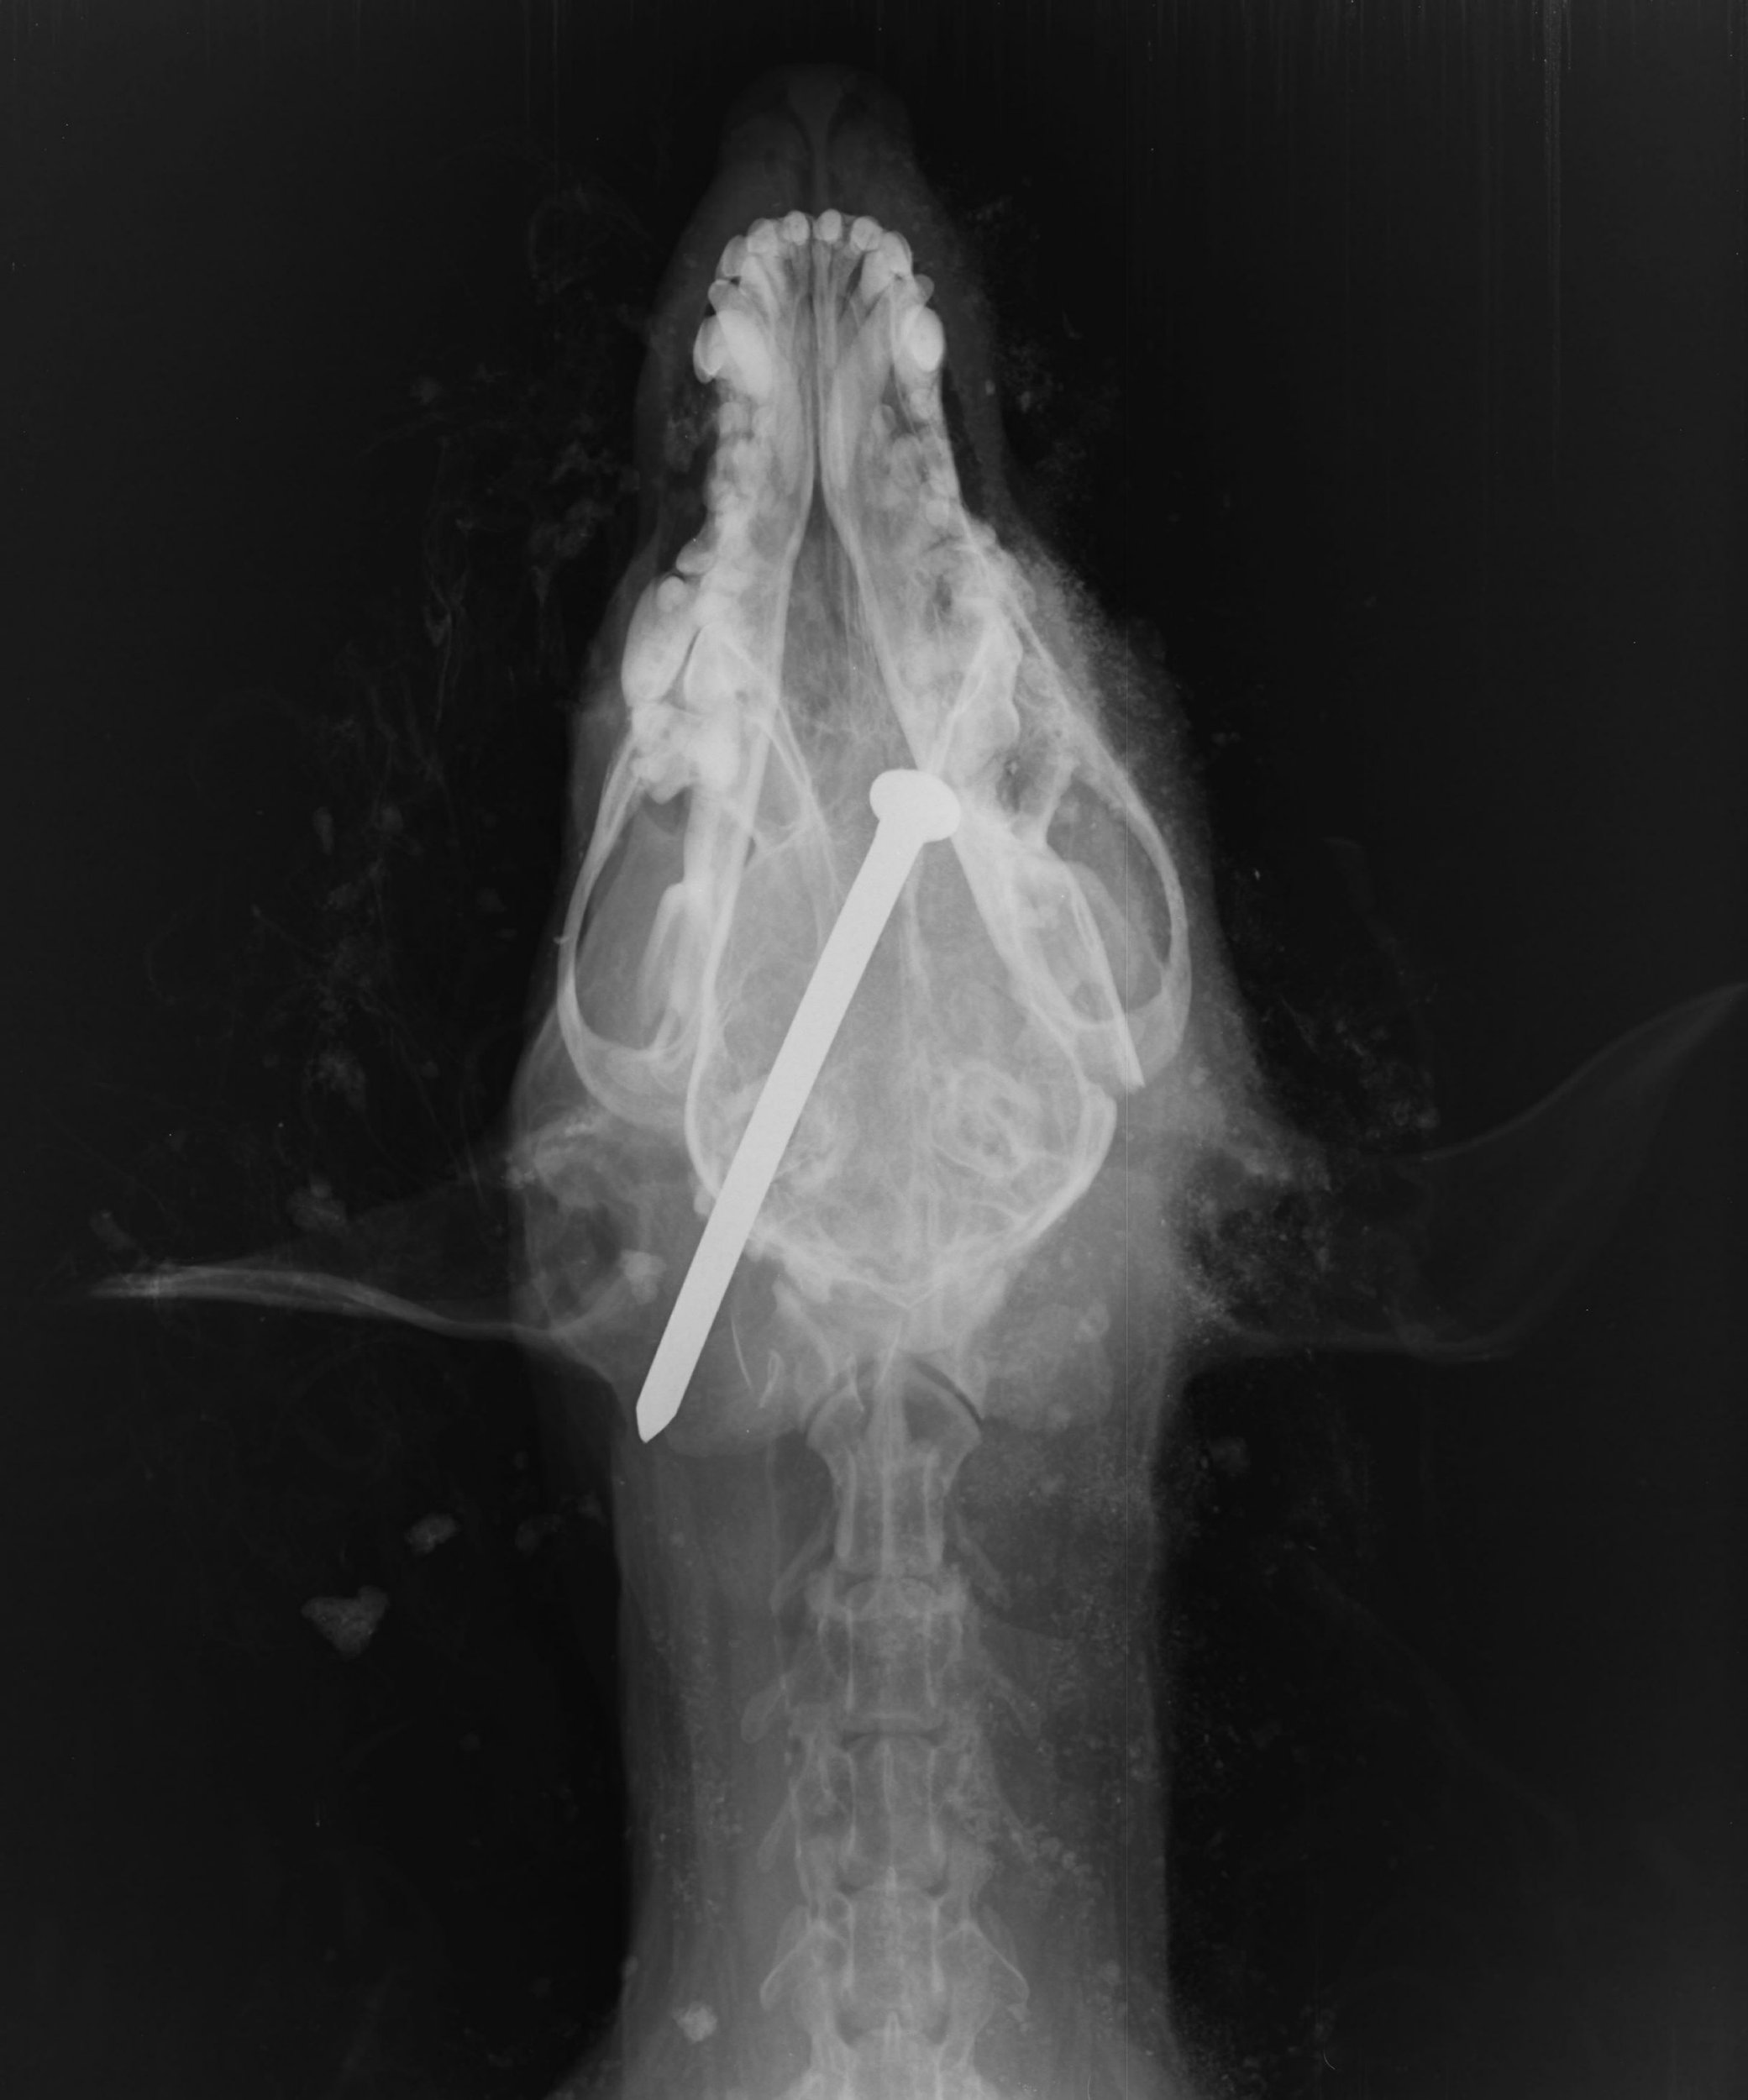

Un barbat a gasit un caine cu un cui batut in craniu, ingropat de viu, in Anglia. Cand l-a descoperit, animalul era in viata.

Barbatul l-a dezgropat si l-a dus la veterinar, insa bietul patruped nu a mai putut fi salvat, asa ca medicii au decis sa il eutanasieze.

Cei de la Protectia Animalelor au facut publice mai multe poze grafice cu animalul pentru a incerca sa-i prinda pe vinovatii acestui atac terifiant.